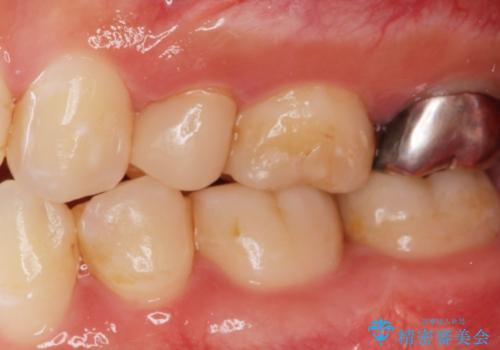

- 他院で被せた保険の白い被せ物(樹脂)をセラミックの被せ物に変えたいとの事で来院。

被せ物を外し、虫歯がないことを確認してセラミックの被せ物(ジルコニアクラウン)の治療を行いました。

白くて適合の良い被せ物が入りました。

セラミックは劣化することがなく虫歯の再発のリスクが低くなります。